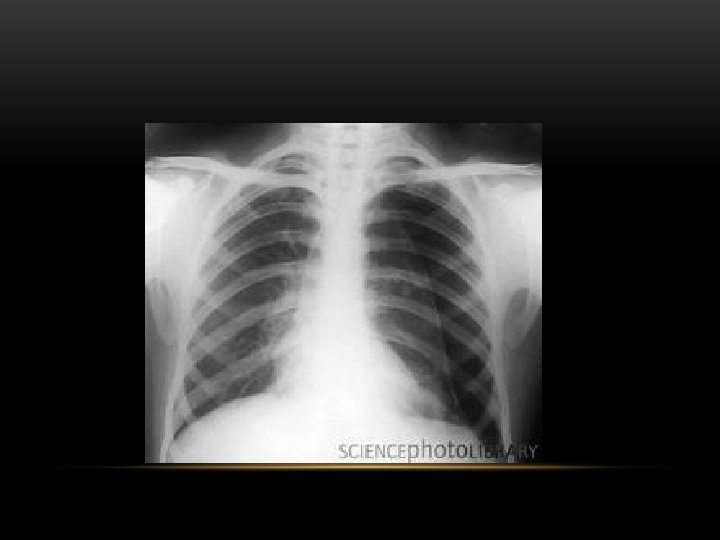

Spontaneous Pneumothorax • Air in pleural space • Lung margin • "Normal lungs": Note the radiolucency of atelectatic lung is the same as the opposite lung